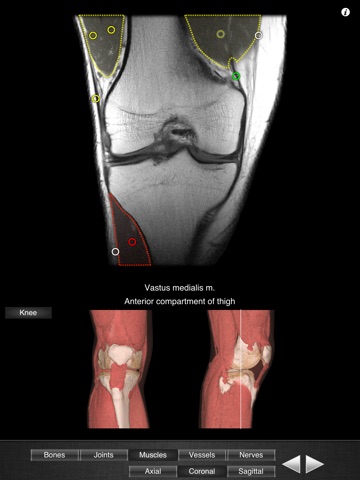

Monster Anatomy - Knee is the free version of Monster Anatomy - Lower limb, an interactive lower limb radiology atlas presented at the 2009 Radiological Society of North America annual meeting. It only contains knee images. The application was developed in the Medical Imaging Department of the University Hospital Center of Nancy, France, under the supervision of Professor Alain Blum. This application is designed for healthcare professionals (Radiologists, General Practitioners, Orthopedists, Surgeons, Physiotherapists among others) as well for students, as a reference and learning tool. It contains 82 contiguous knee MR slices (4-5 mm thickness) in the three anatomical planes. Features: - Intuitive navigation with multiple shortcuts. - Fluid display of images in the three anatomical planes. - 3D Image volume (VR) allows precise location of slice position. - Labels in accordance with the “Terminologia Anatomica" and current literature references. - The five different display modes available (bones, joints, muscles, blood vessels and nerves) facilitates label visualization. - High image quality with a zooming tool. Once the application is installed no network connection is necessary. You can download the full version on the AppStore : "Monster Anatomy - Lower limb" Dont hesitate to give some feedback on the application and to rate and comment on the AppStore! NB : Monster Anatomy - Knee is designed for trained healthcare professionals. This application is not intended as a substitute of patient/healthcare provider interaction or as a replacement of professional judgment.